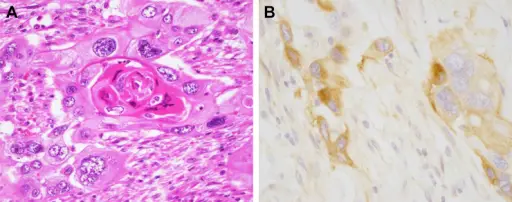

Squamous Cell Carcinoma of the Bladder

The second most prevalent type of bladder cancer is squamous cell carcinoma (SCC) of the bladder.

Squamous cell carcinoma (SCC) of the bladder is characterized by abnormal, accelerated squamous cell proliferation.

The normal bladder surface is not coated with squamous epithelium, hence this cancer develops against a backdrop of squamous metaplasia.

Symptoms of squamous cell carcinoma (SCC) of the bladder include:

- Chronic cystitis in older women

- Infection with Schistosoma haematobium in Egyptian males

- Persistent nephrolithiasis